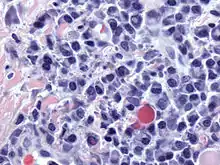

Micrograph of malignant plasma cells (plasmacytoma), many displaying characteristic "clockface nuclei", also seen in normal plasma cells. H&E stain.

Plasmacytoma, multiple myeloma, Waldenström macroglobulinemia, heavy chain disease, and plasma cell leukemia are cancers of the plasma cells.[33] Multiple myeloma is frequently identified because malignant plasma cells continue producing an antibody, which can be detected as a paraprotein. Monoclonal gammopathy of undetermined significance (MGUS) is a plasma cell dyscrasia characterized by the secretion of a myeloma protein into the blood and may lead to multiple myeloma.[34]